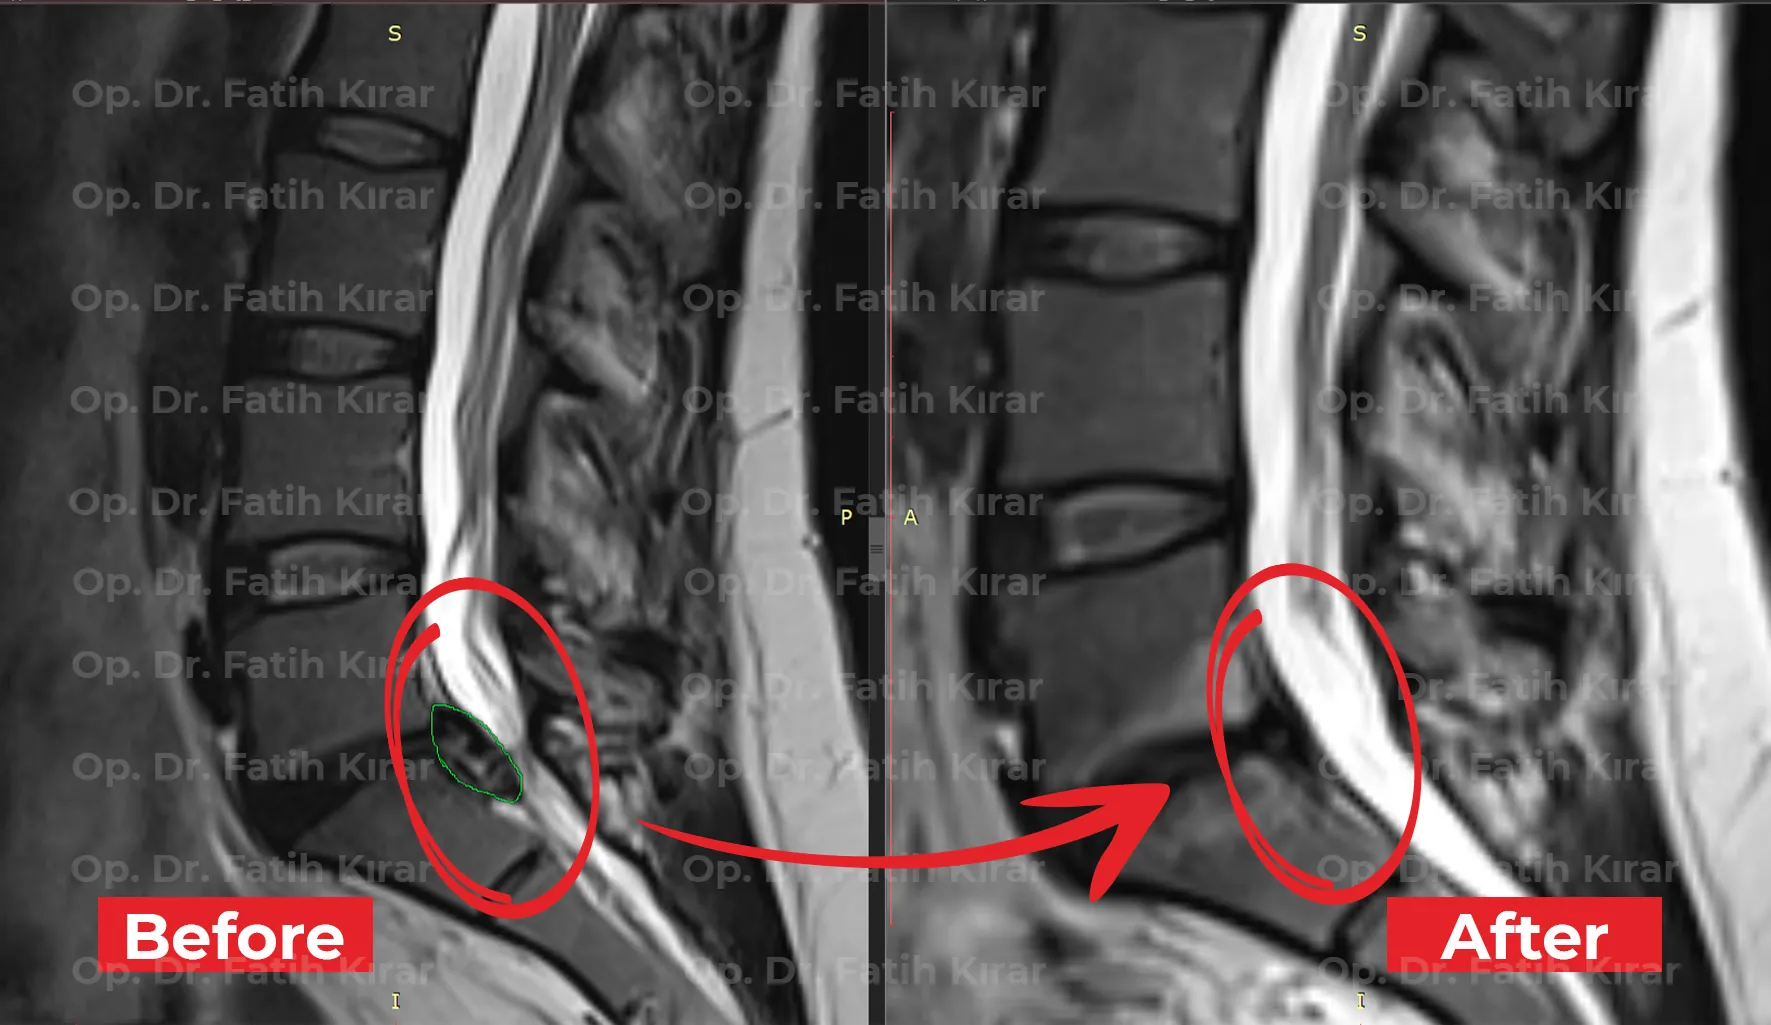

MR Images

Pre and post-treatment MR images of our patients

Former star player of Real Madrid and Spanish National Team Fernando Morientes came to Turkey for back hernia treatment. He regained his health with applied regression and robotic laser treatments.